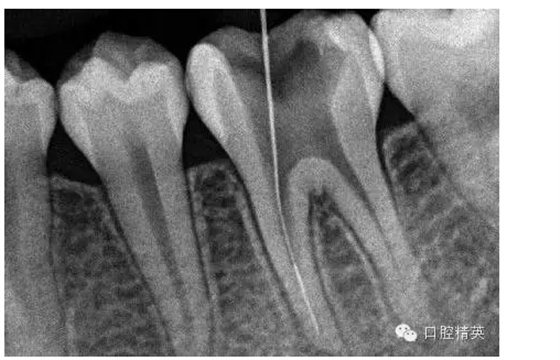

7,找出斷針旁路,未攝片,。。。

8,找到后,直接用超聲根管搓15號帶出斷針。。。

9,斷針取出術(shù)后X-P,RCT待續(xù)。。。